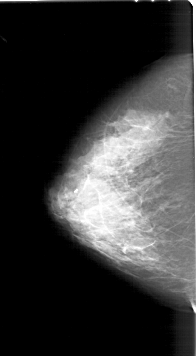

A_1218_1.LEFT_CC

LEFT_CC LINES 6406 PIXELS_PER_LINE 3526 BITS_PER_PIXEL 12 RESOLUTION 43.5 NON_OVERLAY